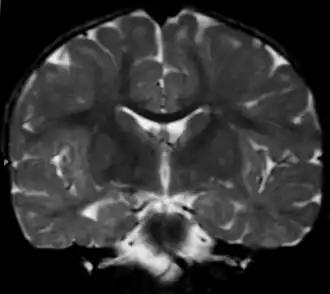

| Вид фронтального среза головного мозга при метахроматической лейкодистрофии (МРТ). | |